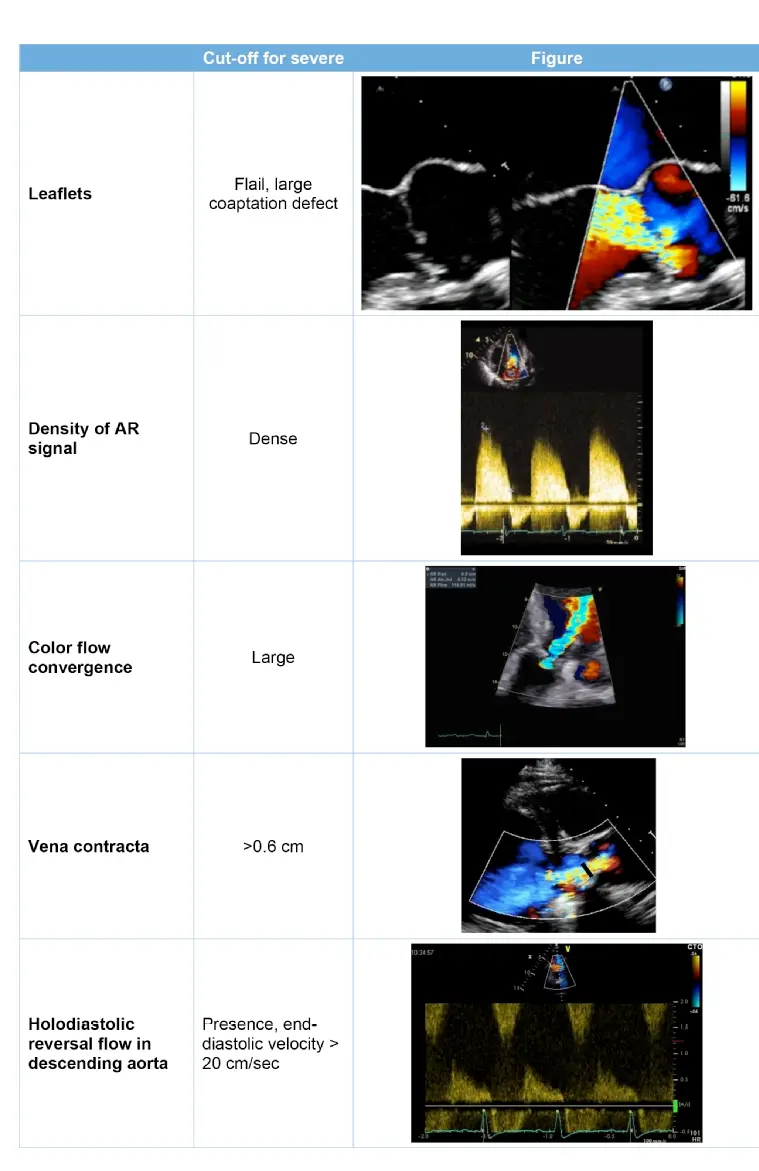

Vena Contracta Width

- A VC < 0.3 cm indicates mild, 0.3-0.6 cm indicates moderate, and > 0.6 cm indicates severe AR.1

- PWD: Holodiastolic flow reversal is an abnormal finding and indicates at least moderate AR; when present in the abdominal aorta, it is consistent with severe AR.

- Holodiastolic reversal (flow throughout diastole) strongly suggests moderate to severe AR

- End-diastolic velocity: a value >20 cm/s in the descending aorta often suggests severe AR, correlating with an aortic regurgitant fraction ≥ 40%